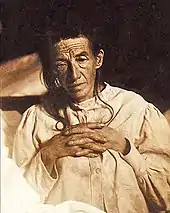

_presenile_onset.jpg.webp)

Alzheimer's disease is characterised by loss of neurons and synapses in the cerebral cortex and certain subcortical regions. This loss results in gross atrophy of the affected regions, including degeneration in the temporal lobe and parietal lobe, and parts of the frontal cortex and cingulate gyrus.[93] Degeneration is also present in brainstem nuclei like the locus coeruleus.[94] Studies using MRI and PET have documented reductions in the size of specific brain regions in people with AD as they progressed from mild cognitive impairment to Alzheimer's disease, and in comparison with similar images from healthy older adults.[95][96]

History

The ancient Greek and Roman philosophers and physicians associated old age with increasing dementia.[18] It was not until 1901 that German psychiatrist Alois Alzheimer identified the first case of what became known as Alzheimer's disease, named after him, in a fifty-year-old woman he called Auguste D. He followed her case until she died in 1906, when he first reported publicly on it.[226] During the next five years, eleven similar cases were reported in the medical literature, some of them already using the term Alzheimer's disease.[18] The disease was first described as a distinctive disease by Emil Kraepelin after suppressing some of the clinical (delusions and hallucinations) and pathological features (arteriosclerotic changes) contained in the original report of Auguste D.[227] He included Alzheimer's disease, also named presenile dementia by Kraepelin, as a subtype of senile dementia in the eighth edition of his Textbook of Psychiatry, published on 15 July, 1910.[228]

For most of the 20th century, the diagnosis of Alzheimer's disease was reserved for individuals between the ages of 45 and 65 who developed symptoms of dementia. The terminology changed after 1977 when a conference on AD concluded that the clinical and pathological manifestations of presenile and senile dementia were almost identical, although the authors also added that this did not rule out the possibility that they had different causes.[229] This eventually led to the diagnosis of Alzheimer's disease independent of age.[230] The term senile dementia of the Alzheimer type (SDAT) was used for a time to describe the condition in those over 65, with classical Alzheimer's disease being used to describe those who were younger. Eventually, the term Alzheimer's disease was formally adopted in medical nomenclature to describe individuals of all ages with a characteristic common symptom pattern, disease course, and neuropathology.[231]